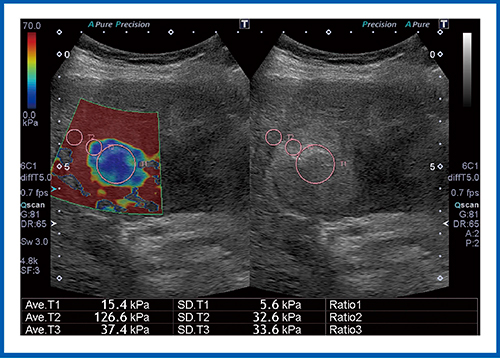

図5はHCC症例であるが,病変が赤く表示され,組織が硬いことがわかる。弾性率は106.7kPaで,非常に硬い腫瘍であった。図6もHCC症例であるが,腫瘍中心部の弾性率は15.4kPaと低く,軟らかい組織である。ただし,背景肝の弾性率は126.6kPaと高く,これはアルコール性肝硬変であることを示している。

図5 HCCのSWE

図6 HCC(アルコール肝硬変)のSWE